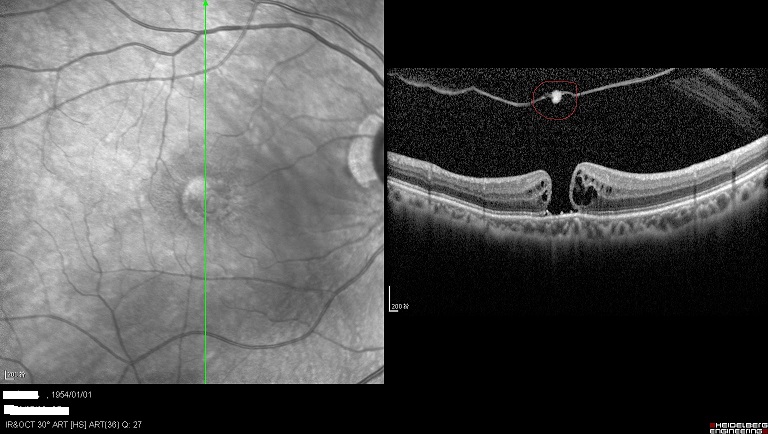

潘阿姨双眼所患的是:“黄斑牵引综合征”,左眼可以看见黄斑区的视网膜被玻璃体牵拉水肿,即将出现黄斑裂孔,而右眼已经是个全层的黄斑裂孔,在黄斑的上方可以看见被牵拉掉的视网膜组织。。

右眼黄斑裂孔,上方可以看见被牵拉掉的组织